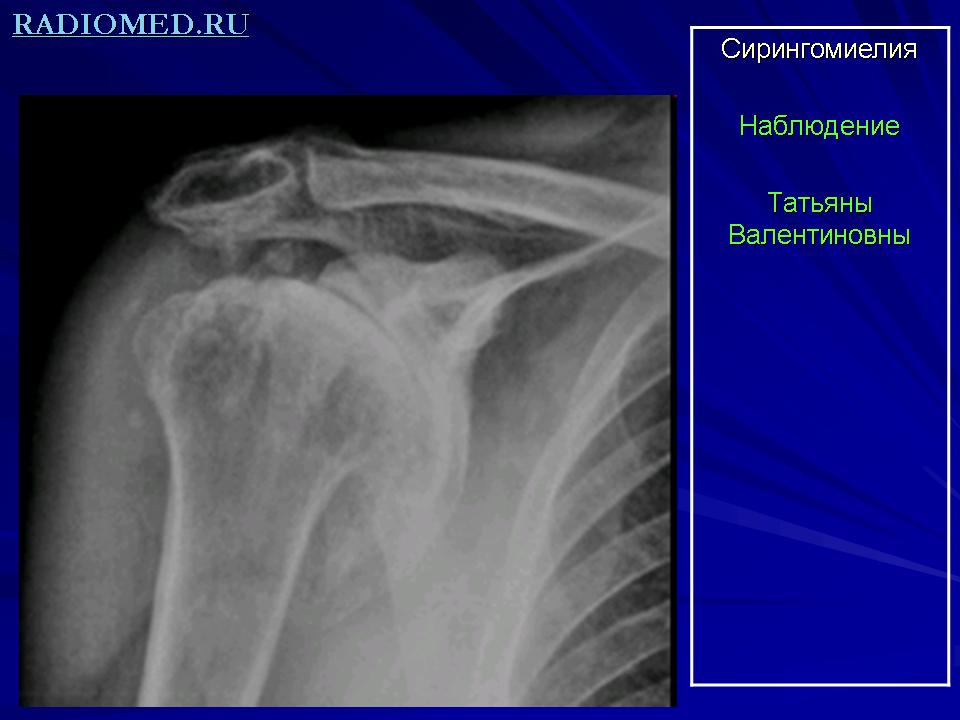

Диагноз. Наличие хронического течения заболевания, характерной клинической картины, состоящей из сегментарного, диссоциированного типов расстройства чувствительности, признаков периферического паралича или пареза верхних конечностей и центрального — в нижних, трофических и вегетативных нарушений, синдрома Бернара—Горнера дают возможность своевременно распознать сирингомиелию. Однако не всегда вышеуказанные симптомы бывают одинаково выражены. Некоторые из них вовсе не обнаруживаются. В таких случаях возникает затруднение в распознавании заболевания. Это требует дополнительных методов обследования больного и дифференциации сирингомиелии от других заболеваний. Таким дополнительным методом являются рентгенография и исследование спинномозговой жидкости. На рентгенограммах костей, особенно верхних конечностей, можно обнаружить остеопороз, деформирующий избыточный рост костной ткани, расщепление позвонков и другие врожденные аномалии. В спинномозговой жидкости обнаруживается белково-клеточная диссоциация.

Диагноз. Наличие хронического течения заболевания, характерной клинической картины, состоящей из сегментарного, диссоциированного типов расстройства чувствительности, признаков периферического паралича или пареза верхних конечностей и центрального  в нижних, трофических и вегетативных нарушений, синдрома БернараГорнера дают возможность своевременно распознать сирингомиелию. Однако не всегда вышеуказанные симптомы бывают одинаково выражены. Некоторые из них вовсе не обнаруживаются. В таких случаях возникает затруднение в распознавании заболевания. Это требует дополнительных методов обследования больного и дифференциации сирингомиелии от других заболеваний. Таким дополнительным методом являются рентгенография и исследование спинномозговой жидкости. На рентгенограммах костей, особенно верхних конечностей, можно обнаружить остеопороз, деформирующий избыточный рост костной ткани, расщепление позвонков и другие врожденные аномалии. В спинномозговой жидкости обнаруживается белково-клеточная диссоциация.